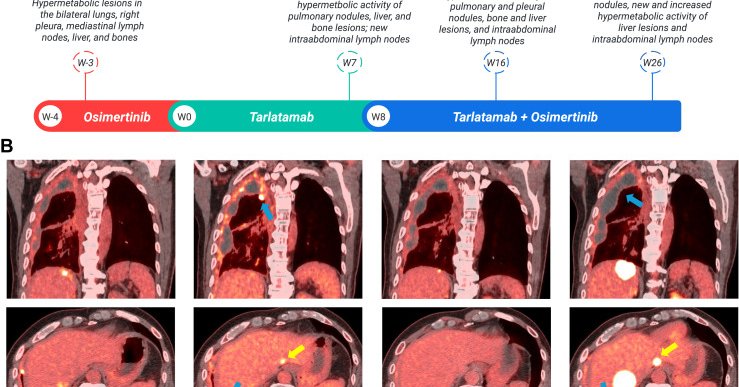

Unfortunately, while DLL3 is widely expressed (93%+) in tumors post-SCLC transformation ( https://t.co/ySAC2zeX7g), it is not clearly an actionable or biologically relevant target for transformed SCLC. This is similar to EGFR alterations and anti-PD-1/PD-L1 therapies, despite high

Disappointing early look at tarlatamab in #EGFR NSCLC after #SCLC transformation @JCOPO_ASCO from @alissajcooper et al. Small numbers but out of 14, only 1 response (7%). May reflect heavy pretreatment and PS but optimism somewhat tempered here. https://t.co/7GKaaXgHp2

Report @JTOonline on DLL3 expression in #EGFR NSCLC after #SCLC transformation. DLL3 positive in 11/12 patients. Two of these patients received tarlatamab (one with osimertinib) with clinical benefit. Need prospective data here! https://t.co/FmnOO32AYR

jtocrr.org

Histologic transformation to high-grade neuroendocrine carcinoma occurs in resistance to EGFR targeted treatment in approximately 3% to 4% of patients with EGFR-mutant lung cancer and is associated...